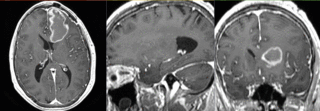

File:RegLib C33 registeredDTI.gif

Size of this preview: 800 × 278 pixels. Other resolutions: 320 × 111 pixels | 928 × 322 pixels.

Original file (928 × 322 pixels, file size: 1.38 MB, MIME type: image/gif)